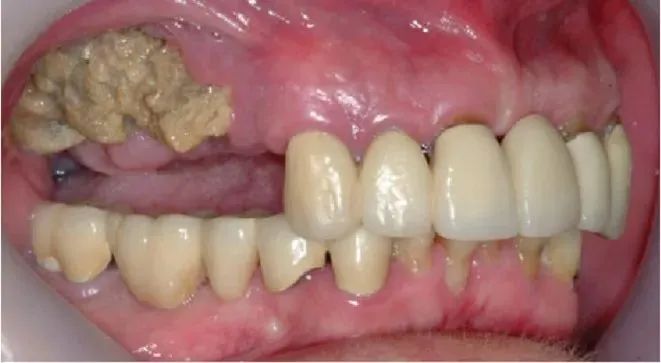

图1 III期药物相关性颌骨坏死患者右上颌局限性大段坏死[2]✦